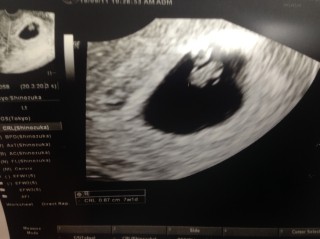

初めての妊娠で、産婦人科へは心拍が確認できる頃に行こうと決めていました。年齢的にも不安があり無事に心拍確認できて嬉しかったです。0.87cm。